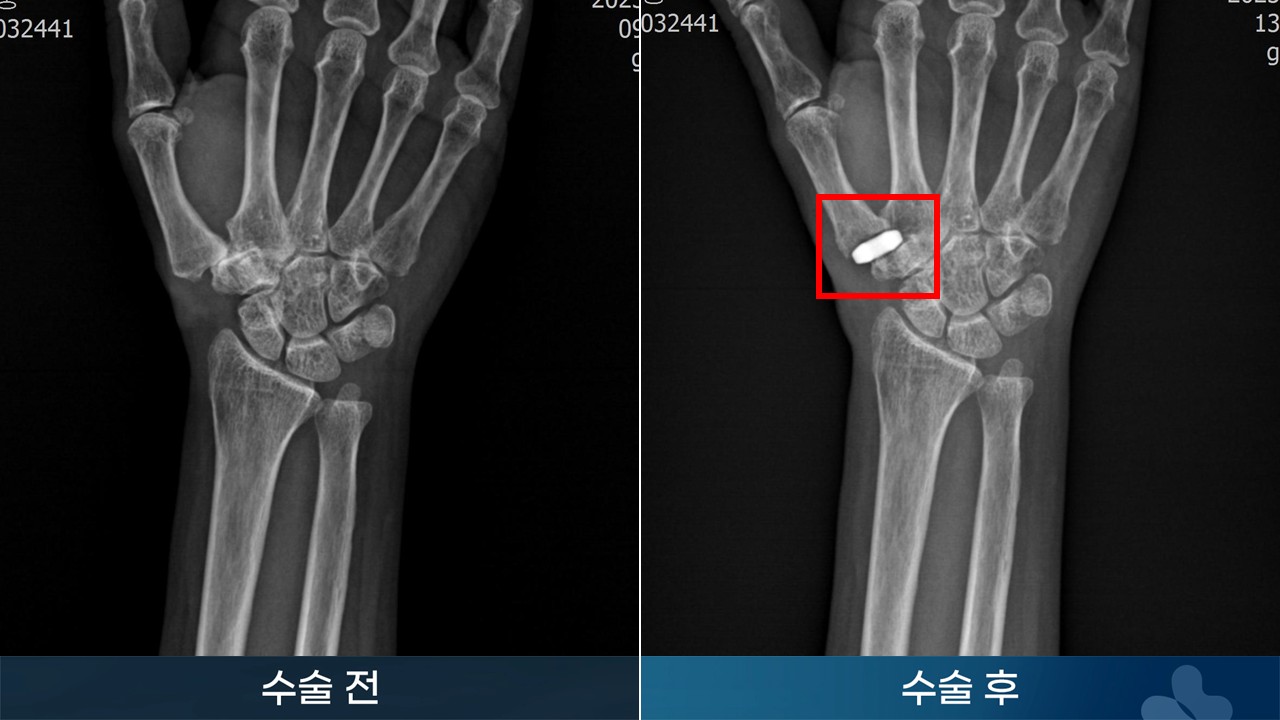

인공관절 수근중수지관절 전치환술